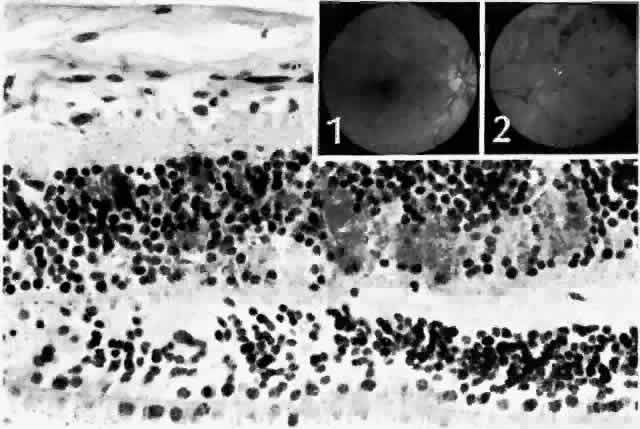

The earliest manifestation of diabetic retinopathy is the appearance of microaneurysms (Fig. 5, Color Fig. D). They appear as small red dots clinically and often are seen more readily on fluorescein angiography, where they fill and leak, with staining of the vessel wall.35 Histologically they are small “outpouchings” of the capillary vessel wall and are usually saccular but occasionally fusiform in shape. They can occur anywhere along the capillary network between the arteriole and venule.18 Some microaneurysms, however, do not fill with fluorescein and have been shown to be thin-walled capillary outpouchings filled with erythrocytes. They may represent either one stage of microaneurysm formation or a specific type of it.36

Fig. 5. Retinal capillary microaneurysm (arrow) is characterized by its thin wall and location in the capillary area of the retina (middle retinal layers) rather than the major vessel area (inner retinal layers). Inset. Fundus appearance of microaneurysms and hard or waxy exudates. (Main figure, H&E, × 176)

Hard exudates clinically appear as shiny yellow deposits (see Fig. 5; Color Fig. D). When they surround a microaneurysm in a circular pattern, the condition is called circinate retinopathy. Histologically, the deposits accumulate at the level of the outer plexiform layer (Fig. 8, Color Fig. E) and consist of lipids, complex carbohydrates, and proteins, as demonstrated histochemically. Hard exudates are normally asymptomatic unless they involve the macula, where they cause a drop in visual acuity. If a leaking microaneurysm can be identified on fluorescein angiography, laser photocoagulation can obliterate it. Over time, the fluid is resorbed, and sometimes visual acuity can improve.40

Fig. 8. Hard or waxy exudates. Retinal exudates accumulate in the outer plexiform (Henle's fiber) or in inner nuclear (bipolar cell) layers. Note that in this case the middle limiting membrane separates the layers. Inset. Fundus appearance of a moderate background diabetic retinopathy. (Main figure, H&E, × 220)

In some patients, the cystoid spaces can coalesce, forming lamellar or full-thickness macular holes.42 Other nonproliferative changes include intraretinal hemorrhages. Flame-shaped hemorrhages occur in the nerve fiber layer, and dot-blot hemorrhages occur in deeper retina, in the outer plexiform and inner nuclear layers (Fig. 9).

Fig. 9. Dot and blot hemorrhages consist of small collections of blood in the inner nuclear and outer plexiform layers of the retina. Insets. Fundus appearance of dot (1) and blot (2) hemorrhages, respectively. (Main figure, H&E, × 260)